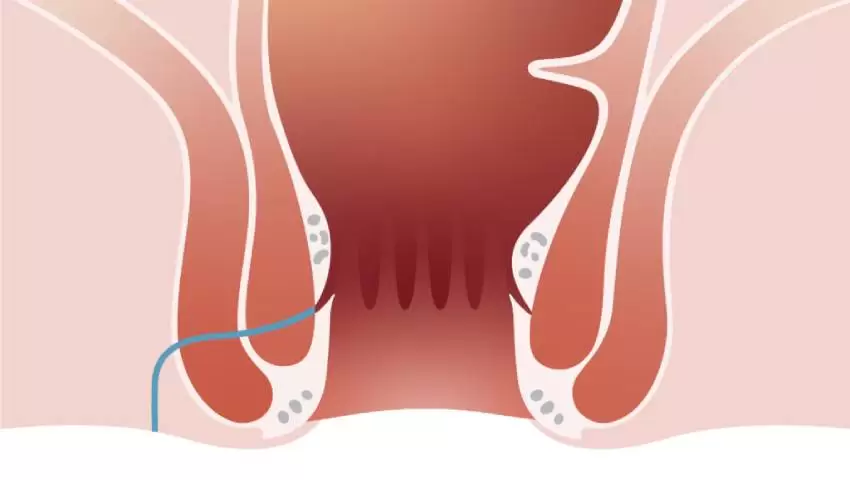

VAAFT is a modern minimally invasive treatment for anal fistula using a fine camera to locate and clear the tract internally without large incisions. Faster healing, low pain & quicker recovery.

VAAFT (Video-Assisted Anal Fistula Treatment) is a modern, minimally invasive, sphincter-saving technique used to treat anal fistulas,

Read More

VAAFT (Video-Assisted Anal Fistula Treatment) is a modern, minimally invasive, sphincter-saving technique used to treat anal fistulas,

Read More